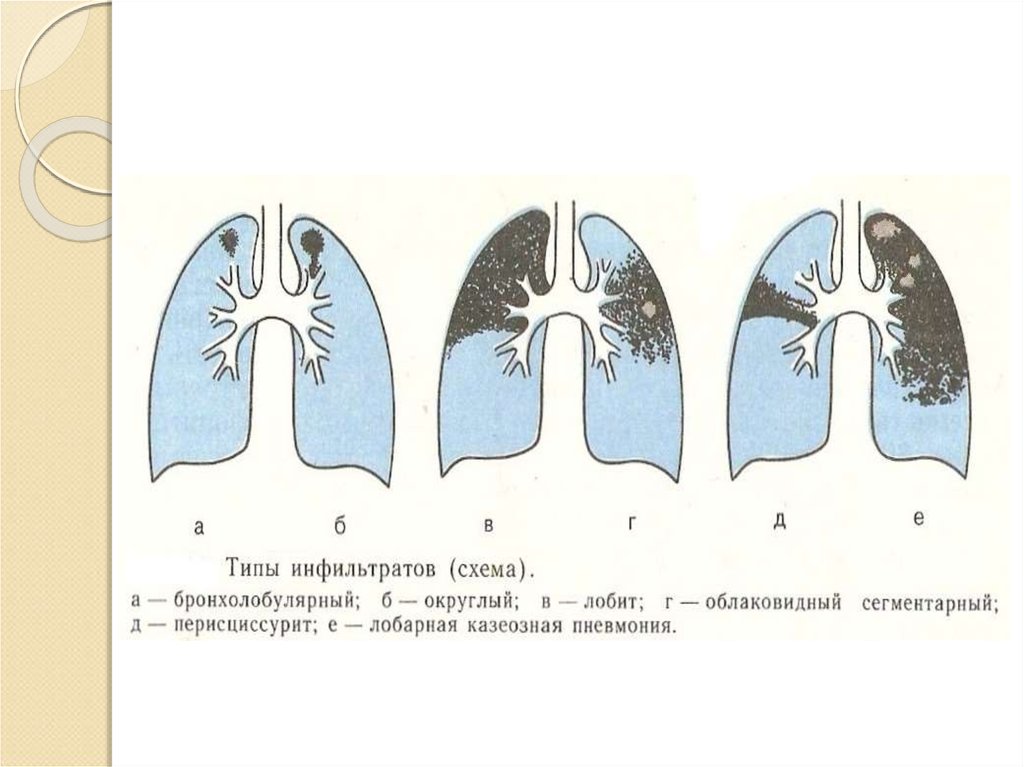

Очаговый и инфильтративный туберкулез презентация - 94 фото